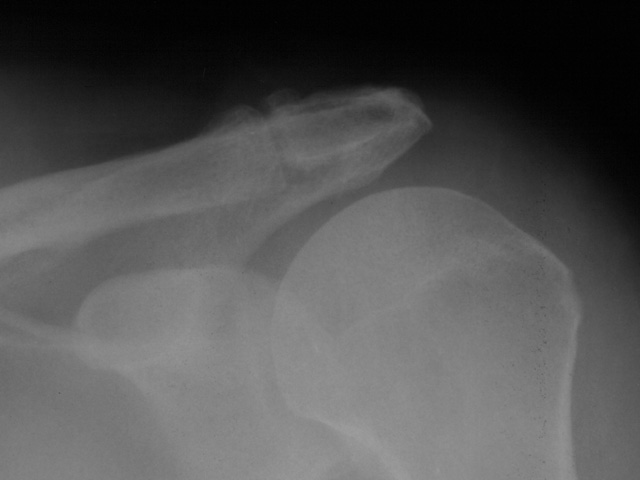

To provide an opportunity for the comparison of image scanning techniques, we are posting in the "Digital Images" forum of the HWB Home Page (http://www.hwbf.org/hwb/) an AP Shoulder film scanned with a $16,000 Howtek Scanmaster DX Xray scanner and a $200 "Snappy" video digitizer. The "Snappy" plugs into the video port of a camcorder or VCR. JPEG compression of either 5:1 or 10:1 are applied to the scans. We would be interested in any feedback with respect to the diagnostic quality of these images.

ROW 1: JPEG 10:1 compression